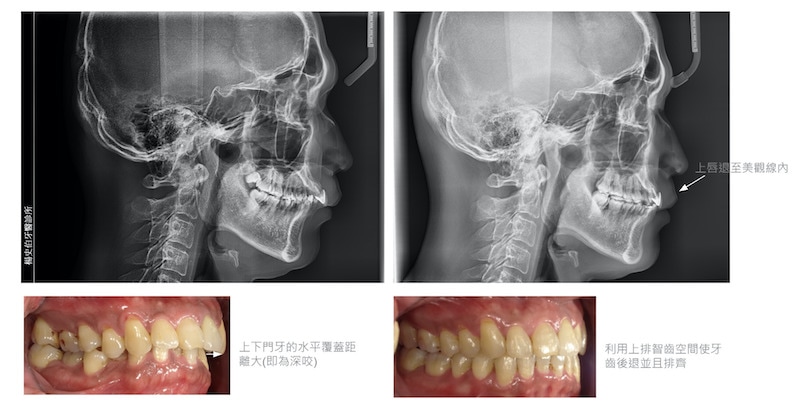

牙齒擁擠、深咬、上下門牙水平距離大

/治療方式

利用上排智齒的空間 搭配 TAD 錨定裝置及橡皮筋將上排牙齒往後退

牙齒矯正前後外觀及牙齒變化